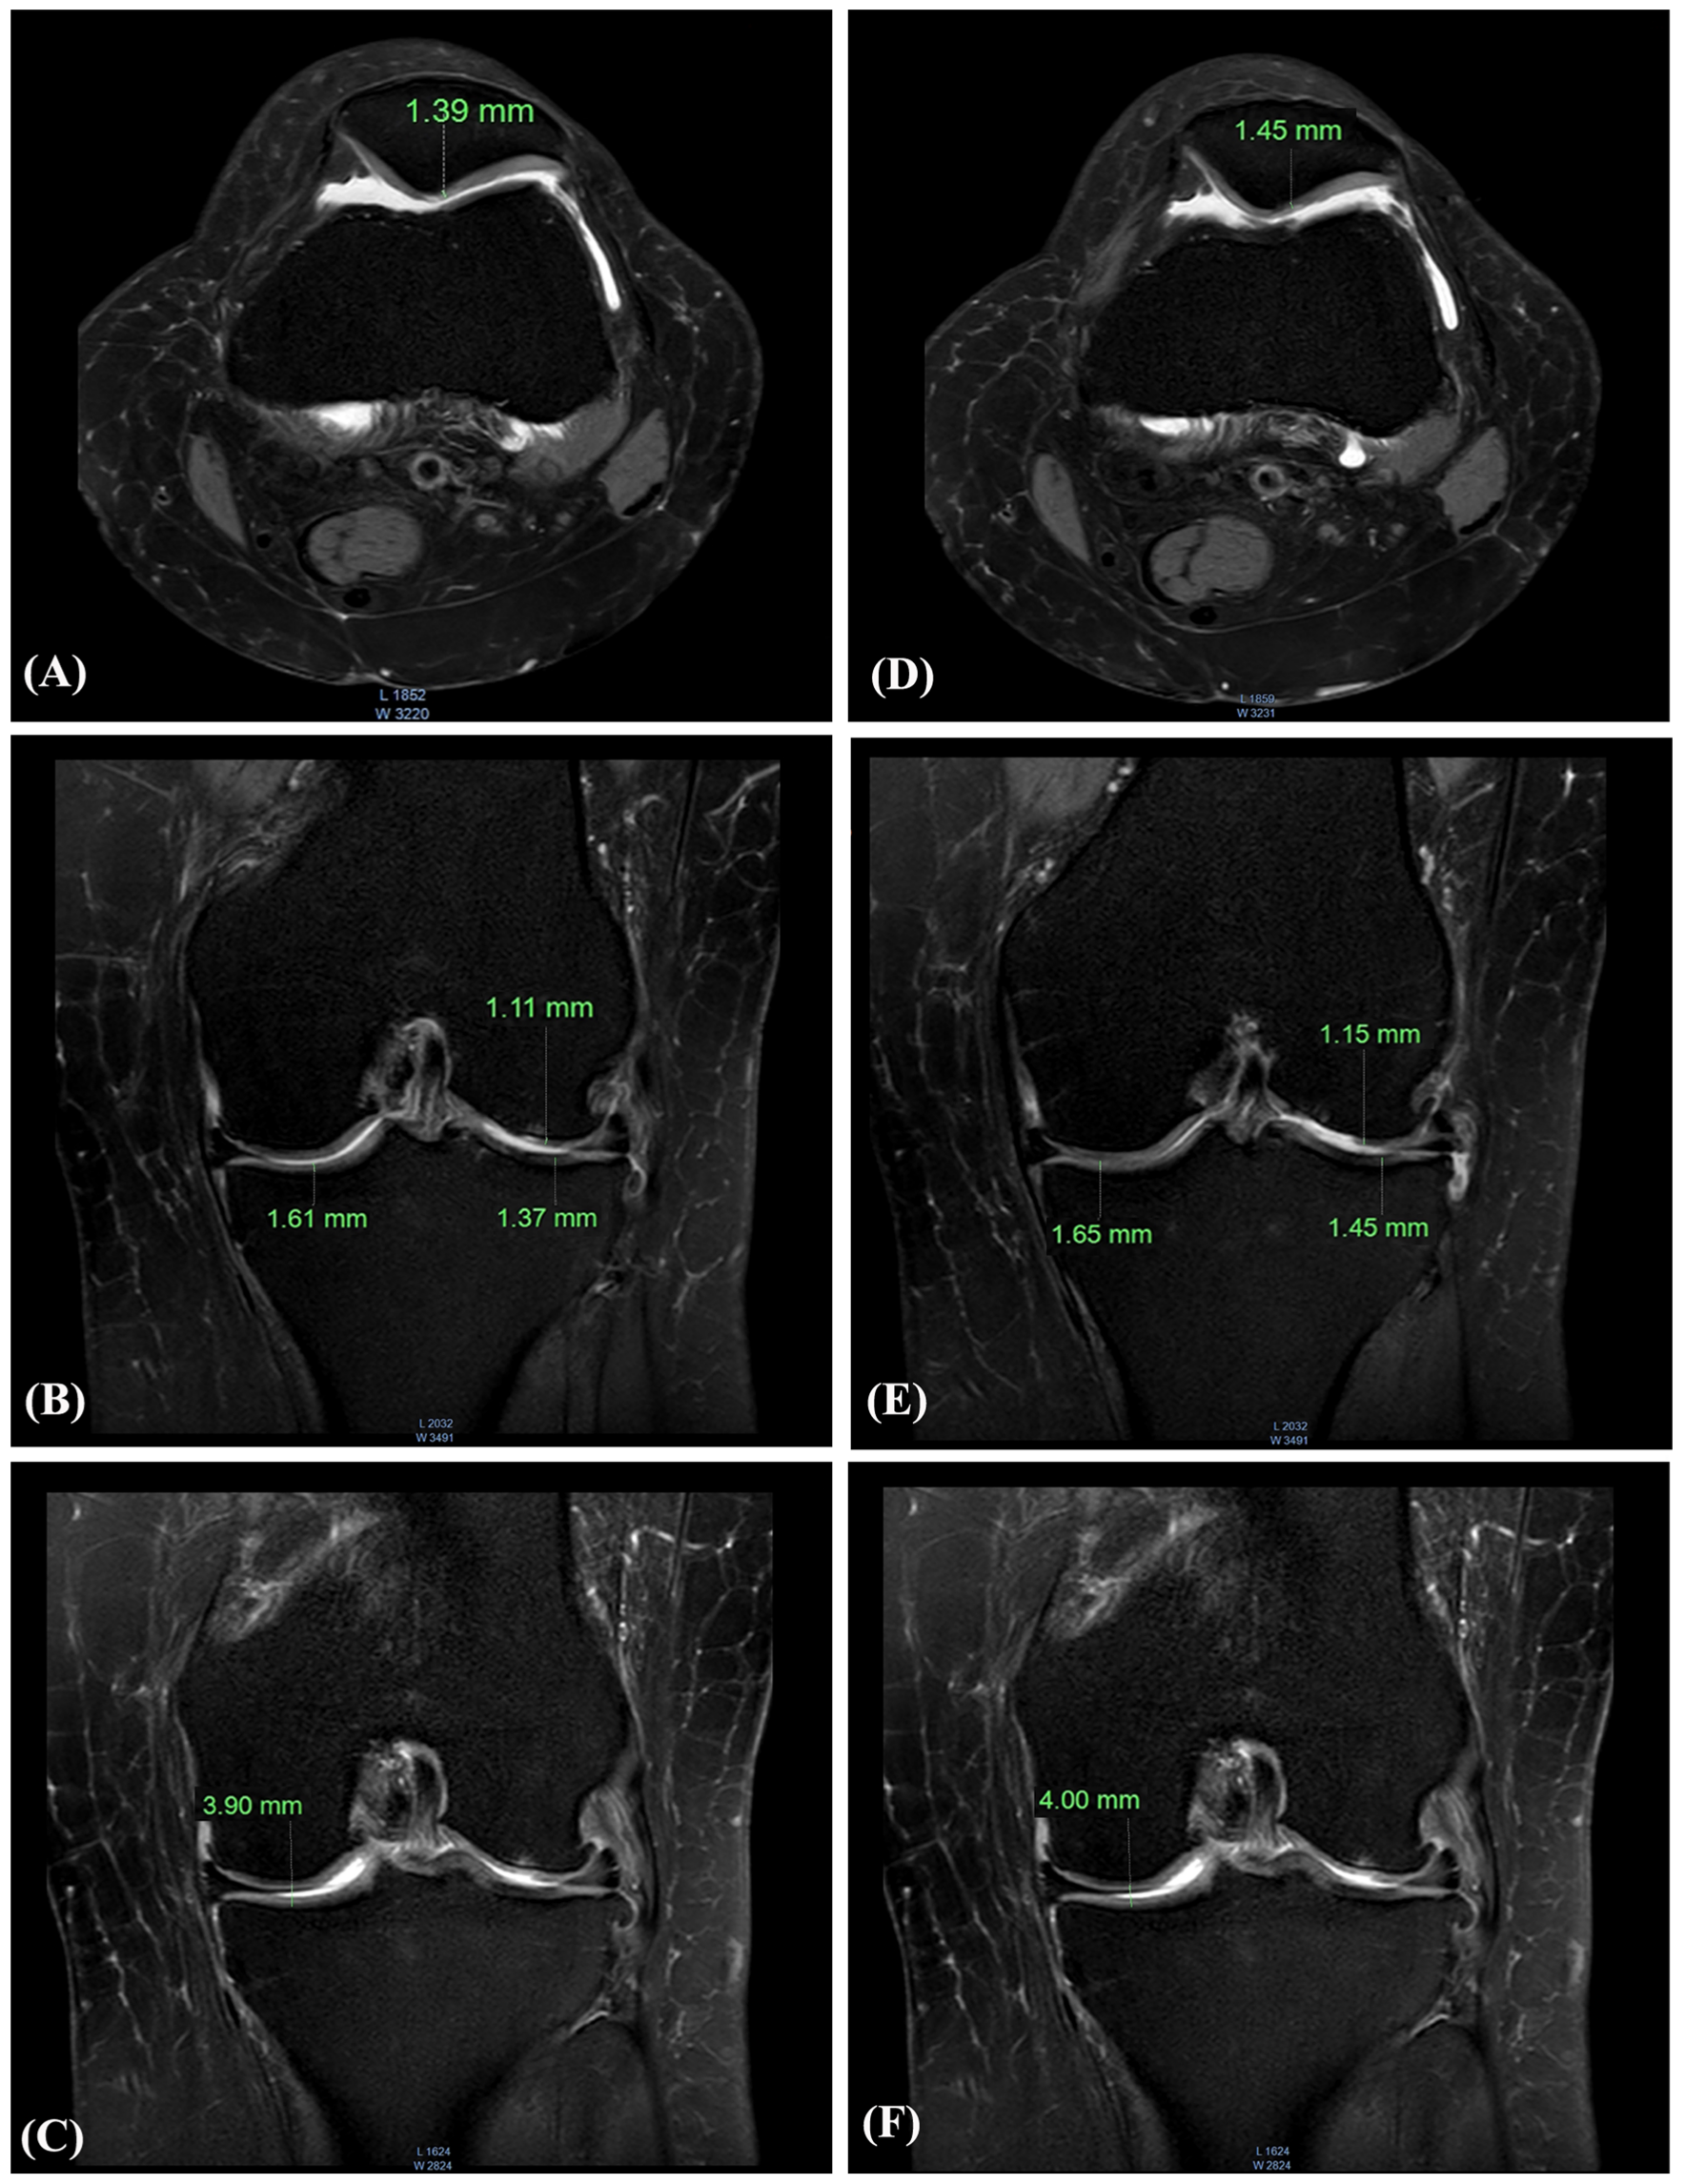

These MRI scans from a 47-year-old female participant show measurable increases in knee cartilage thickness after six months of daily AprèsFlex supplementation. The imaging reveals improvements in both the medial and lateral compartments of the knee, along with increased joint space width.[1]

The study included side-by-side MRI comparisons showing baseline versus day-180 measurements. For one 47-year-old female participant, medial tibial cartilage thickness increased from 1.37mm to 1.45mm, while lateral measurements improved from 1.61mm to 1.65mm. Joint space width expanded from 3.90mm to 4.00mm.

These may seem like small numbers, but in the context of osteoarthritis, a condition characterized by progressive cartilage loss, any increase is remarkable. Most interventions aim to slow degradation. AprèsFlex appears to support regeneration.